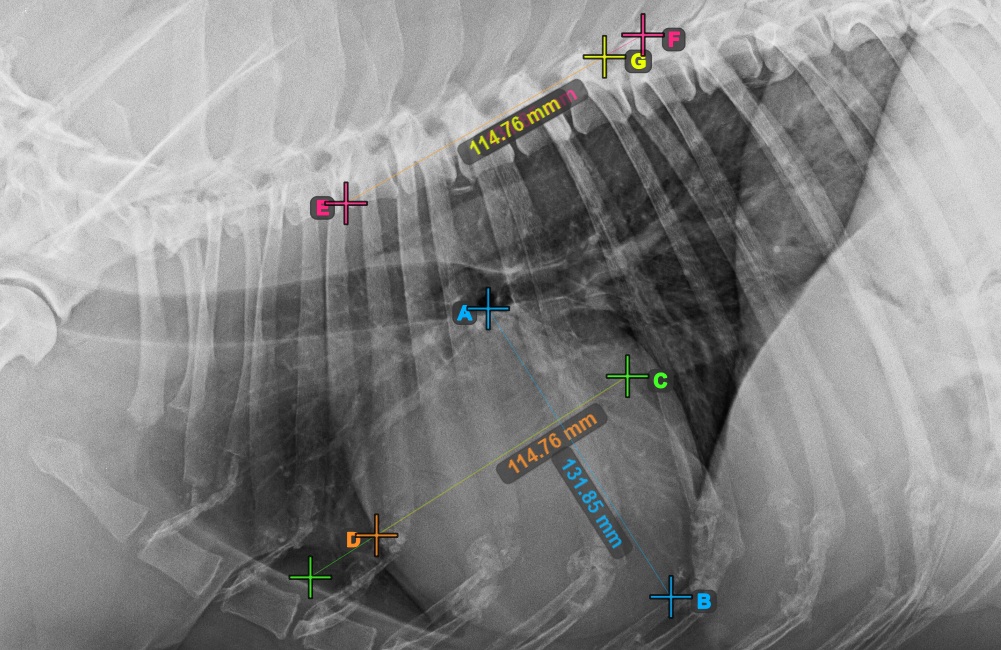

Fejezze be a szív rövid tengelyét a legszélesebb bal (caudal) pont megjelölésével.

Az alábbi kép a szív rövid tengelyének „legcaudalisabb” tipikus elhelyezkedését mutatja.

../../_images/image396.jpg

Azonosítsa a T4 csigolya kezdetét (a gerinc negyedik csigolyatestét), a gerinc kezdőpontjától számítva. Jelölje meg a T4 csigolya kezdetét a mérés folytatásához. A szoftver a megjelölt pontból vonalakat húz a gerinc mentén. A vonalak hossza a szív mért hossz- és rövidtengelyétől függ.

Az alábbi kép a gerinc negyedik csigolyatestének kezdetén lévő pont tipikus elhelyezkedését mutatja.

A szükséges VHS-kalkulációk elvégzése előtt győződjön meg róla, hogy a vonalak pontosan a csigolyák mentén helyezkednek el.